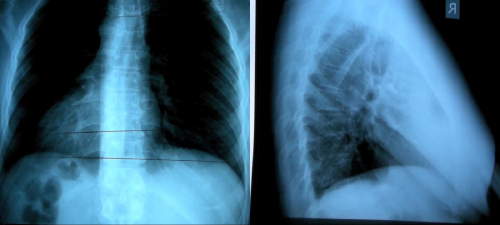

X-Ray Analysis – x-ray films enable your doctor to visualize the entire structure of your spine. This is helpful in evaluating posture, joint and disc integrity, vertebral misalignments and ruling out any pathologies, or recent fractures that may be present or contributing to the patient’s condition. These full-spine radiographs are taken in the standing, weight-bearing position to fully substantiate the examination findings.